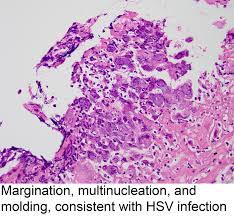

Herpes simplex virus multiple superficial ulcers are common (details from endoscopy) biopsy edge of ulcer — intranuclear inclusions found in squamous mucosa can see detached squamous cells as well as macrophages with viral incusions in ulcer slough inclusions are usually obvious Herpes esophagitis, however, is usually an opportunistic infection but can also occur in immunocompetent. The key feature is acantholysis with solitary keratinocytes within the blister cavity (figures 1,2,3). Ulcers can coalese and form black esophagus histology will show eosinophilic intranuclear inclusions (cowdry type a) and multinucleated squamous cells surrounding the ulcers on biopsy; It can be a consequence of viremia, reactivation of hsv, or even a direct spread of the virus to esophageal mucosa from the vagus nerve in immunocompromised patients. Herpes esophagitis is an inflammation of the esophagus due to herpes simplex virus. Herpetic esophagitis (eh) caused by herpes simplex virus (hsv) usually affects immunocompromised patients, as a primary infection or as a reactivation of a previous infection. Herpes esophagitis is a viral infection of the esophagus.

#2 most common cause of infectious esophagitis after candida self limited in healthy patients; Abstract herpes simplex virus (hsv) is a common cause of infectious esophagitis. Esophagitis caused by herpes simplex virus (hsv) is frequently documented during periods of immunosuppression in patients infected with human immunodeficiency virus (hiv). Ultimate gut formula that heals your esophagus naturally with 4 powerful nutrients. It can occur in immunocompromised patients as well as healthy individuals over a wide age range, including children and young adults. Know the real cause of esophagitis & how to heal your digestive system naturally. The key feature is acantholysis with solitary keratinocytes within the blister cavity (figures 1,2,3). The ulcer base at the left shows loss of overlying squamous epithelium with only necrotic debris remaining. Human papillomavirus is detectable in barrett's esophagus and esophageal carcinoma but is unlikely to be of any etiologic significance.. J clin virol 50 (3): Following these findings, the patient received intravenous acyclovir. Herpes simplex virus multiple superficial ulcers are common (details from endoscopy) biopsy edge of ulcer — intranuclear inclusions found in squamous mucosa can see detached squamous cells as well as macrophages with viral incusions in ulcer slough inclusions are usually obvious Can perform cmv immunostain if no classic viral cytopathic effect seen on h&e.